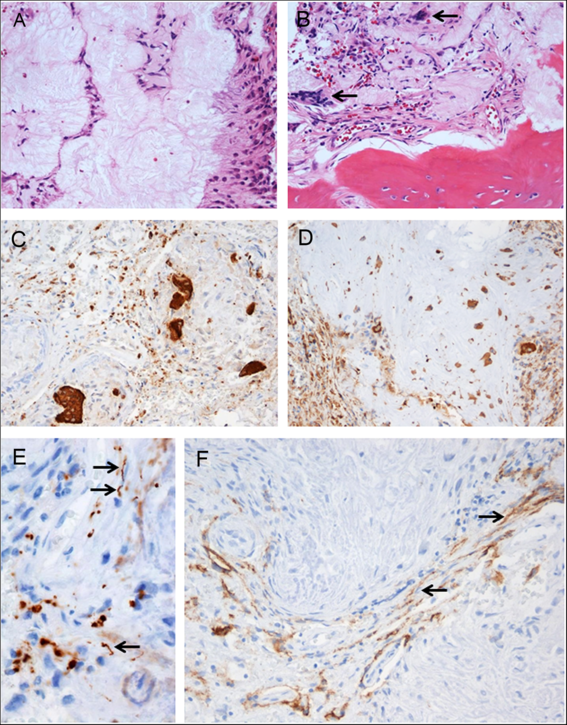

Pathological examination of the resected tissue revealed a fibro-osseous lesion with cores of amorphous to fibrillary materials, peripheral palisading of spindle to epithelioid cells, multifocal calcifications and ossifications, as well as occasional multinucleated giant cells (Figure 2A and B), which was diagnostic of CAPNON. Immunohistochemistry showed focally scattered CD68-positive macrophages including multinucleated giant cells (Figure 2C) and vimentin positivity in most spindle to epithelioid cells (Figure 2D). Neurofilament protein (NFP) immunostaining demonstrated focally positive axons at the periphery of this lesion, suggestive of CN involvement and correlating with the clinical findings of cranial neuropathies (Figure 2E). The lesion exhibited limited epithelial membrane antigen (EMA) positivity in cells or membranes at the periphery of amorphous core (Figure 2F).

Figure 2: Photomicrographs of the right cerebellopontine angle calcifying pseudoneoplasm of the neuraxis. The lesion contained cores of granular amorphous to fibrillary materials with peripheral palisading spindle to epithelioid cells (A), calcification/ossification, and occasional multinucleated giant cells (B, arrows). Immunohistochemistry revealed focally scattered CD68-positive macrophages including multinucleated giant cells (C), vimentin+ in most spindle to epithelioid cells (D), peripherally located NFP+ axons (E, arrows pointing longitudinally sectioned axons; transversely sectioned axons shown as positive dots), and limited EMA+ cells or membranes at the periphery of amorphous core (F, arrows pointing the membranes). Original magnification, ×200 (A–D, F), and ×400 (E).

Since the first characterization of CAPNON as an osseo-fibrous lesion in 1978, over 100 cases of CAPNON have been reported. The average age at presentation is 47 years and a slight male predilection is seen.Reference Barber, Low, Johns, Rich, MacDonald and Jones5 With regard to spinal CAPNONs, they are typically located in the epidural space (81.48%).Reference Garcia Duque, Medina Lopez, Ortiz de Mendivil and Diamantopoulos Fernandez6 In contrast, intracranial CAPNONs are more commonly found intra-axially.Reference Alshareef, Vargas, Welsh and Kalhorn4–Reference Garcia Duque, Medina Lopez, Ortiz de Mendivil and Diamantopoulos Fernandez6 In this study, we reviewed a total of 24 cases located at the skull base and discovered a high incidence (45.8%) of cranial neuropathies associated with skull base CAPNONs. In our case report of a right CPA CAPNON, we present novel pathological findings of the CN involvement with NFP-positive entrapped nerve fibers/axons identified at the periphery of the lesion, correlating with clinical cranial neuropathy.

Pathologically, CAPNONs are distinctly different from grossly calcified, psammomatous meningiomas and metaplastic meningiomas. CAPNON is typically composed of the following components: (1) chondromyxoid cores containing amorphous to fibrillary materials; (2) peripheral palisading of spindle to epithelioid cells; (3) calcifications and ossifications; and (4) foreign-body reaction with multinucleated giant cells.Reference Qian, Rubio and Powers23 Despite high variations in these morphological components, the chondromyxoid cores with calcification seem to be a principal constituent of CAPNON. On the other hand, psammomatous meningiomas consist of abundant psammoma bodies (more than half of the tumor) with intermixed meningothelial cells.Reference Liu, Lu and Peng25 Metaplastic meningiomas are characterized by mesenchymal differentiation including osseous, cartilaginous, lipomatus, xanthomatous, and/or myxoid tissue elements, with retained meningothelial cells in nonmetaplastic areas.Reference Caffo, Caruso, Barresi and Tomasello26,Reference Tang, Sun and Chen27 EMA immunostaining, a routinely used marker for meningiomas, is positive largely in the retained meningothelial cells in metaplastic and psammomatous meningiomas. In contrast, CAPNONs have limited EMA positivity that is often linear in distribution and typically seen at the periphery of the amorphous cores or the tissue edge of CAPNONs,Reference Aiken, Akgun, Tihan, Barbaro and Glastonbury3 which may be reflective of the meningeal involvement in the stroma rather than the constituent of CAPNONs. In the 24 reviewed cases of skull base CAPNONs, EMA immunostaining was positive with or without specified distribution in 6 cases (including our 2 cases),Reference Blood, Rodriguez, Nolan, Ramanathan and Desai14,Reference Fletcher, Greenlee, Chang, Smoker, Kirby and O’Brien15,Reference Kerr, Borys, Bobinski and Shahlaie17,Reference Wisniewski, Janczar, Tybor, Papierz and Jaskolski24 but negative in 2 cases,Reference Hodges, Karikari and Nimjee16,Reference Nussbaum, Hilton and Defillo20 and not mentioned in the remaining 16 cases. We speculate that EMA is usually negative in CAPNONs without the meningeal involvement or focally positive in CAPNONs with the meningeal involvement, and its positivity is limited to the meningothelial cells entrapped in CAPNON lesions. Therefore, EMA is a useful pathological marker to differentiate CAPNONs from calcified psammomatous or metaplastic meningiomas (Table 2).

The morbidity associated with CAPNONs arises primarily from mass effect. Intracranial CAPNONs can cause seizures, headaches, vision loss, weakness, pain, and developmental delay.Reference Kerr, Borys, Bobinski and Shahlaie17 Additionally, our systematic review of the literature found that CAPNONs at the skull base are associated with a high incidence of cranial neuropathies (45.8%). This may be partially explained by mass effect exerted on CNs by the lesion around the narrow neural foramina. It could also be related to the inflammatory nature of CAPNON. As illustrated in our right CPA CAPNON case, nerve axons have been at the periphery of the lesion, which may reflect inflammatory “invasion” of the nerves and explain the high incidence of cranial neuropathies.